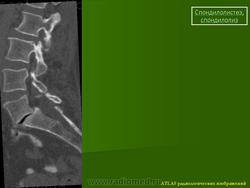

Рис.3a,b,c. Истмический спондилолистез (спондилолиз). a) Рентгенограмма поясничного отдела позвоночника. Стрелкой указана зона дефекта (спондилолиза) дужки L5 позвонка. b) Компьютерная томограмма (КТ) L5 позвонка. Стрелкой указана зона дефекта (спондилолиза) дужки L5 позвонка. с) Магнитно-резонансная томографи (МРТ) поясничного отдела позвоночника. Стрелкой указано смещение L5 позвонка кзади I степени.